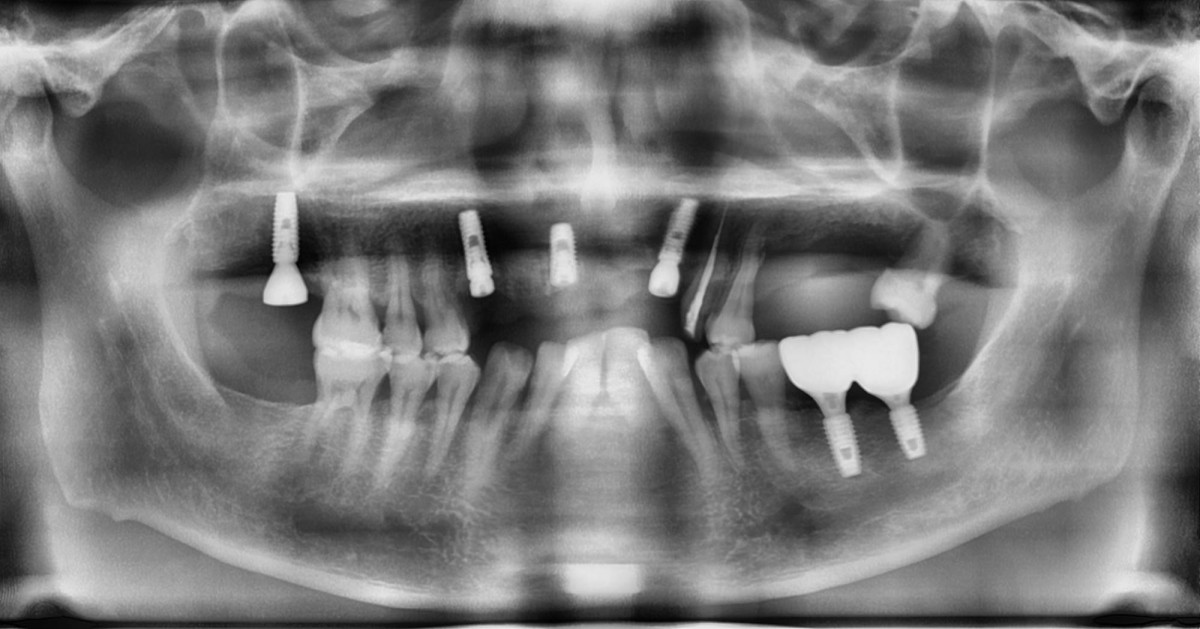

In the anterior maxilla, implant-supported fixed partial denture.

<GCpbc> A 58-year-old male is a patient undergoing implant installation in various parts. The old Br of the anterior maxilla has fallen

off and it is no longer possible to maintain it even temporarily, so a

treatment plan for the anterior teeth was made.